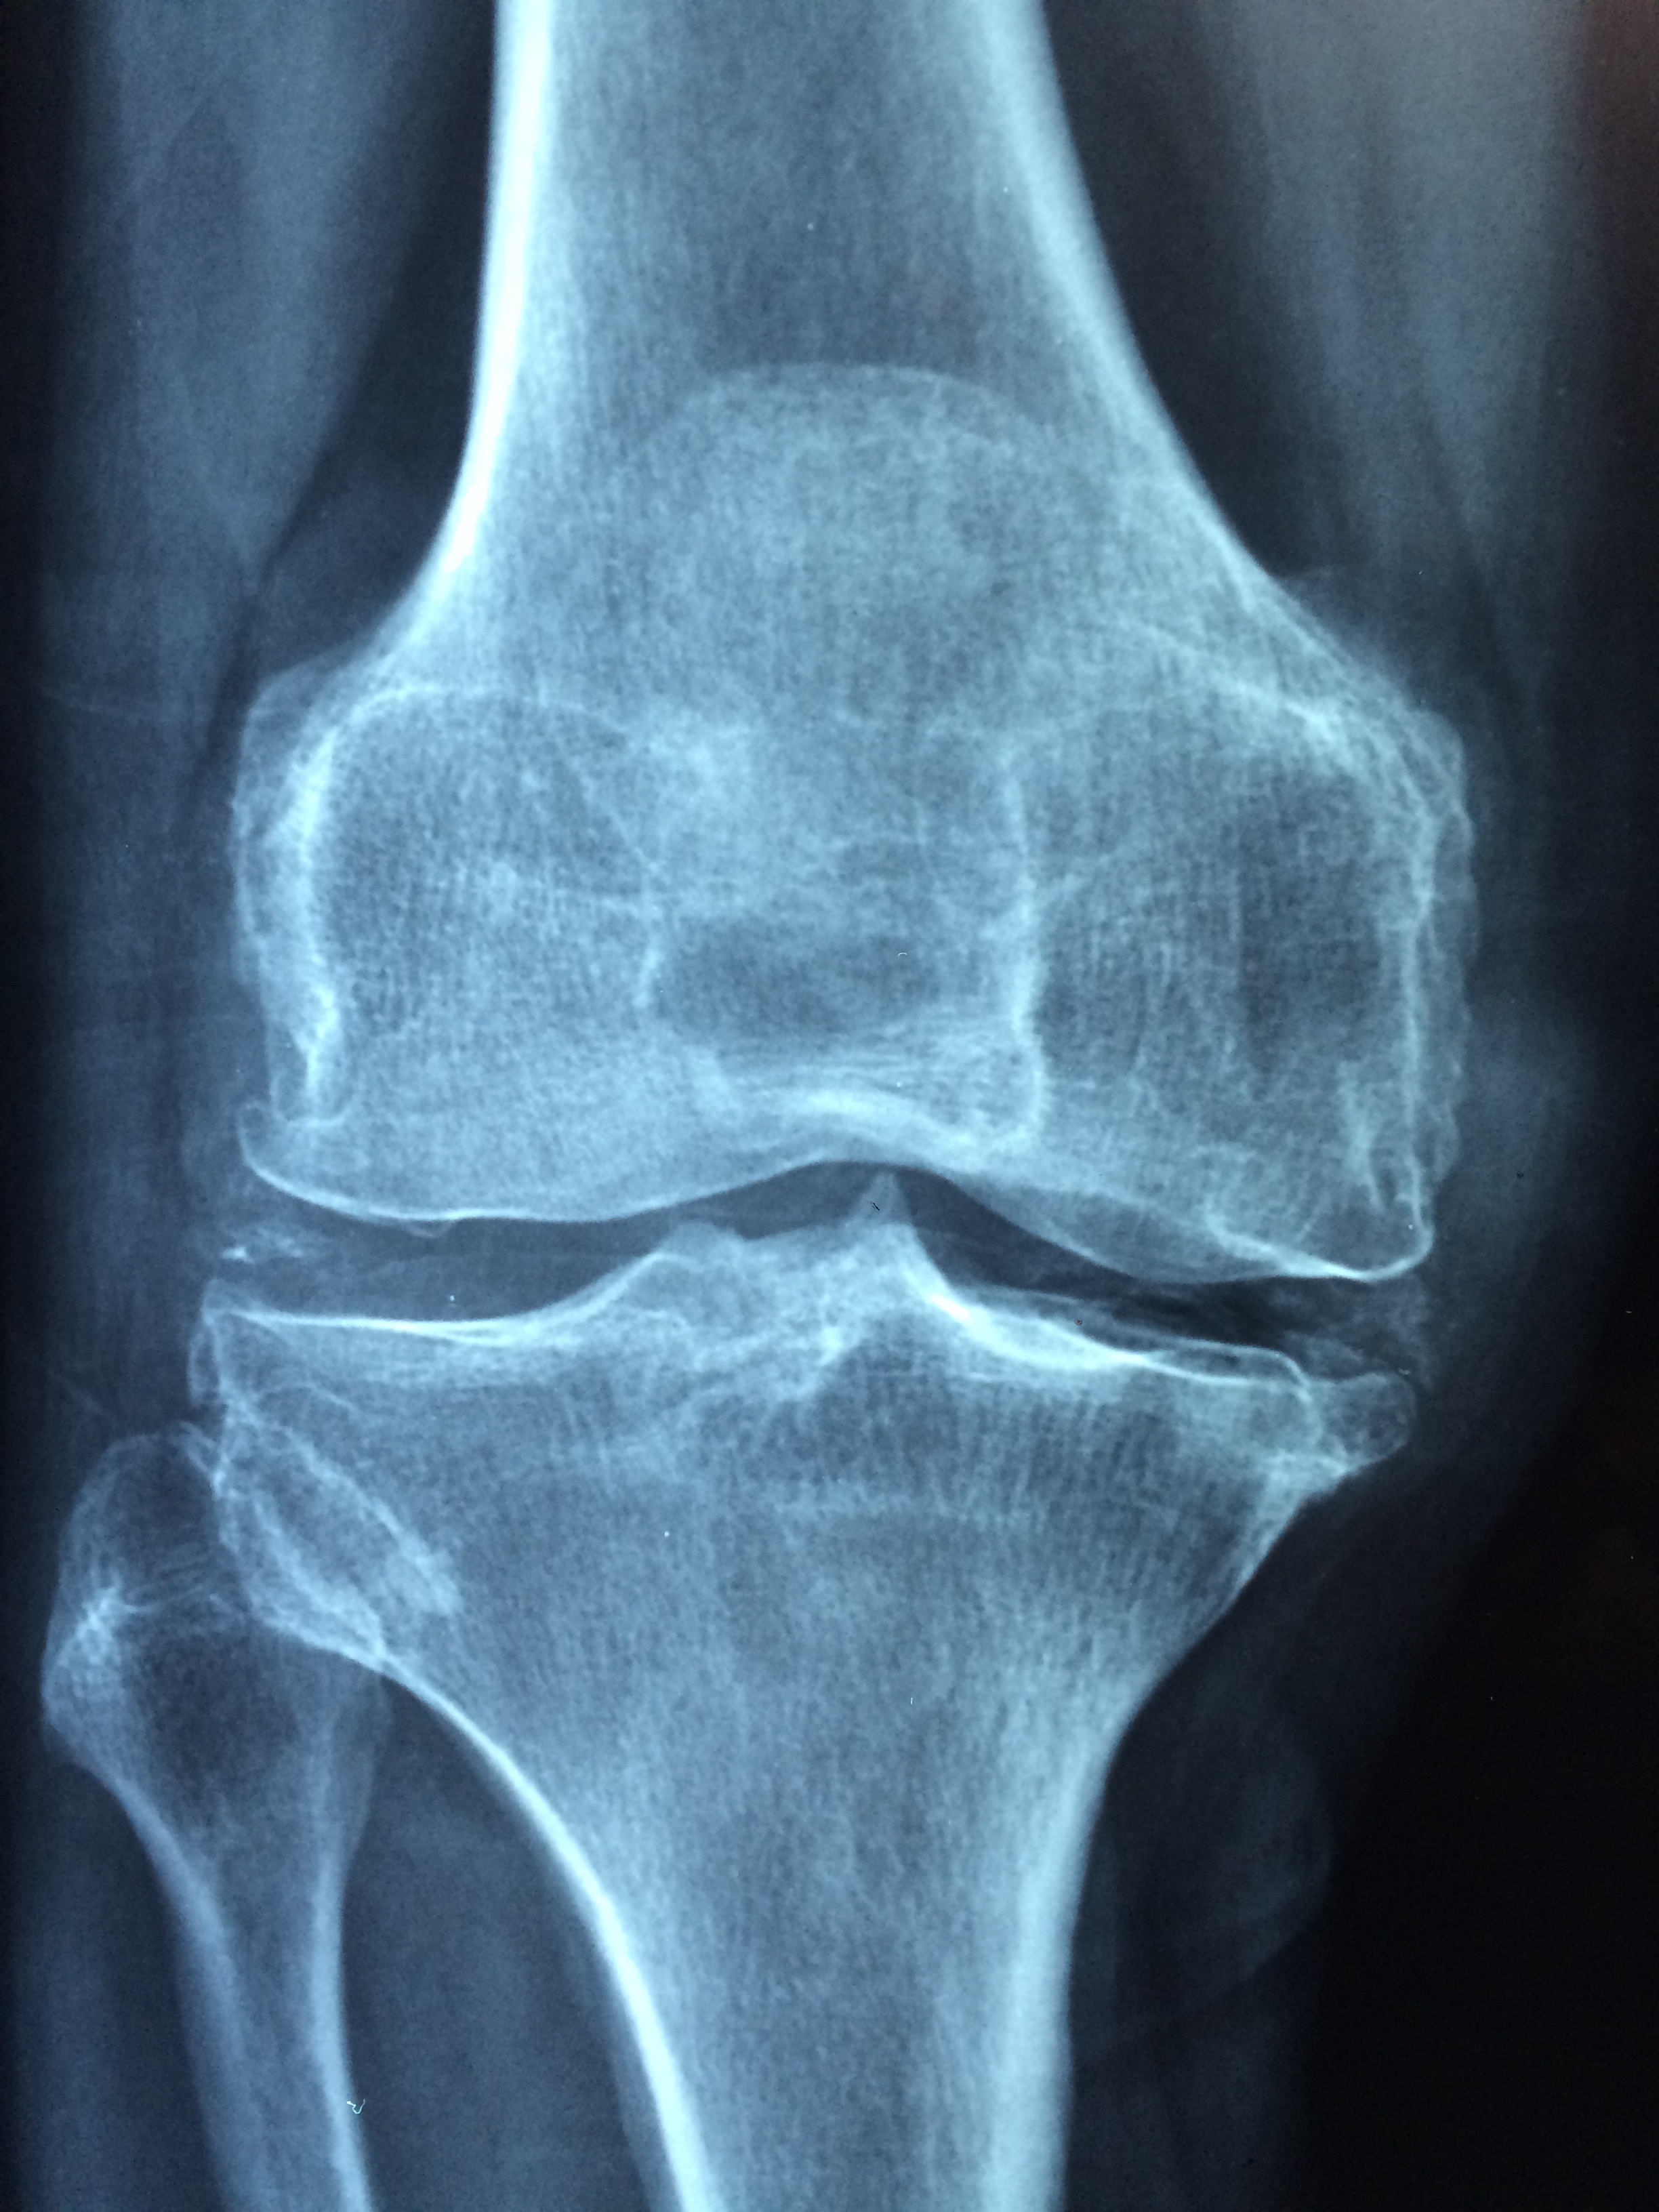

There are of course other less common issues that can cause knee problems too. When people say running will ruin your knees they’re talking long term. In other words a condition that will lead to lots of long term pain, disability and potentially a knee replacement. That is symptomatic Osteoarthritis (OA). So we have two things to figure out here, does running cause knee injuries and does it in fact in the long term kill your knees?

In a word no. The studies and meta studies we’ve examined to this point are of people with knee injuries showing up at sports clinics or even just of runners showing up at clinics. Now it’s time to look at the other side of the coin and that is people with symptomatic (see disabling) knee issues. Were a higher than average proportion of those people runners? Again in a word no. It’s important to know that Osteoarthritis of the knee is the most common cause of disability over 60 years of age (Bosworth, 2009).

One study surveyed all osteoarthritis patients over 10 years. The were asked about their lifetime exercise habits up to that point. There was no increased risk of symptomatic osteoarthritis in patients that identified as runners at some point in their life (Lo et al., 2016).

Weird right? Thousands of people with ruined knees studied and the runners in the group were no worse off or even represented at lower numbers? That can’t be right! Well let’s look deeper. Does physical activity ever pose a risk for one’s knees well the answer is actually yes. Physical activity is associated with an increased risk of knee osteoarthritis. However the level of activity required is pretty extreme. Patients who did more then 4 hours of heavy physical activity a day were at increased risk. Patients who did 3- 4 hours or less daily were not any more likely to develop OA (McAlindon et al., 1999). However if you are a person who does heavy physical labour or exercise for a living there is a warning here. You might want to talk to your doctor next time you’re in to ask what you can do to minimize damage to your knees over time.

Last argument then… Does running make OA worse? If you’ve got the first signs of arthritis in your knees you should stop running right? Again that’s a hard no. A meta study of patients with OA compared those that didn’t exercise compared to those that did and moderate exercise did not accelerate progression of the arthritis including running (Bosomworth 2009). So even if that niggle in your knee is the first signs of arthritis that’s not a reason to stop either.

Wait a minute might running actually protect your knees from OA? Well yes there is reason to believe that this is the case. One study followed the older members (above 50) of a running club for 18 years and compared their knees to those of control subjects who never ran. Guess what the runners didn’t develop any more OA over the next two decades than those in the controls! In fact they had less and a higher BMI was the only lifestyle factor linked to developing arthritis (Chakravarty et al., 2008). In a similar study of running club members not only did the runners exhibit a rate of disability several times lower than the general public controls they also had a much lower mortality rate even when other lifestyle factors were controlled for (Fries et al., 1994). Not only do older runners have fewer knee problems, way less of them are disabled and fewer of them are dead! Now if that’s not an advertisement for running I don’t know what is! And as one final (giant) nail in the running is bad for your knees argument I present a meta study of over 125 000 participants which found that the incidence of knee OA in competitive (elite) runners was 13%, in recreational runners 3% and in control populations 10% (Alentorn-Geli et al., 2017). Now that’s a big finding with a really big n! So no, running does not ruin your knees as a recreational runner it actually protects them. That means that a recreational runner is more than three times less likely to develop OA than the person telling them that running will damage their knees. Even if your make your living running you’re only 3% more likely than someone in the general population to someday develop arthritis. That’s probably a fair trade off for all the very lucrative Instagram sponsored posts right?